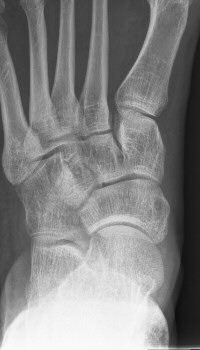

Första bilden med normal navikulare, andra bilden med accessorisk navikulare typ 2, tredje bilden typ 3.